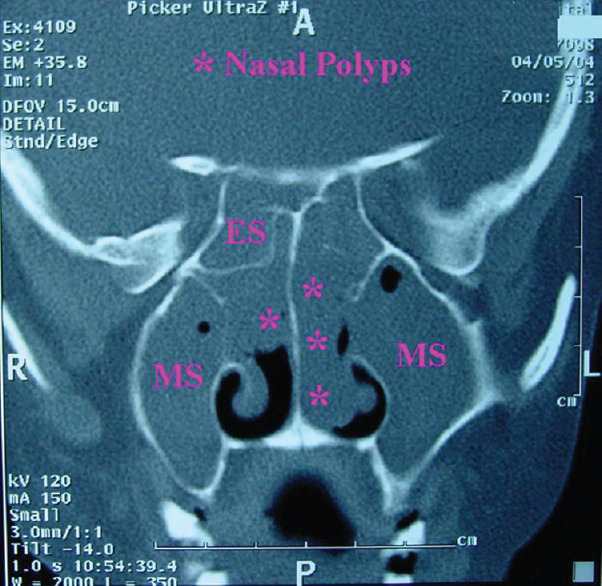

Background: Patients having nasal polyposis who do not respond to medical management are subjected for functional endoscopic sinus surgery (FESS). One of the most common complications of surgery is bleeding. One of the strategies to reduce bleeding and securing a dry operating field during surgery is the use of preoperative corticosteroids which shrink the polyps and decrease mucosal inflammation.